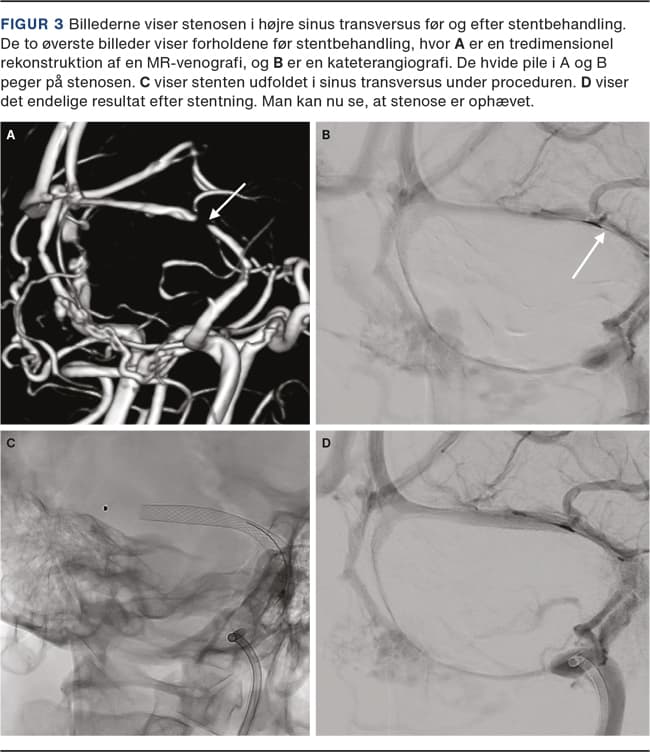

IIH grupperes ofte sammen med sygdomsgruppen hydrocephalus, men ved IIH er ventrikelsystemet grundet det høje venøse tryk normalt eller komprimeret i modsætning til hydrocefalus, hvor ventriklerne er dilaterede. De radiologiske tegn, som kan ses ved IIH, inkluderer empty sella, væskeophobning langs nervi optici og andre kranienerver, abnormt snoede nervi optici, posterior affladning af øjeæblerne (Figur 1) og stenose af sinus transversi (Figur 2) [6]. Disse tegn kan anvendes til at støtte diagnosen IIH hos patienter uden papilødem, hvilket er nærmere beskrevet af Jensen et al.

Såfremt der er bilaterale sinus transversus-stenoser eller unilateral stenose med modsidig hypoplasi samt en hæmodynamisk betydende trykgradient over stenosen, vil der være indikation for behandling [17]. Et kateter indføres UL- eller gennemlysningsvejledt via en punktur i halsvenen, og en guidewire føres retrogradt til sinus transversus. Under tilbagetrækningen af katereret udløses en selvekspanderende stent, som dækker stenosen (Figur 3). Der er sjældent behov for supplerende ballonangioplastik. Hjernens venesystem visualiseres simultant med indirekte cerebral angiografi med et kateter placeret i a. carotis interna via en lyske- eller håndledspunktur. Adskillige studier har vist, at stentning af stenoserne har effekt med ophævelse af den transstenotiske gradient og lindring af symptomerne [20].